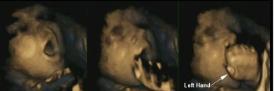

Babies learn how to anticipate touch while in the womb

Using 4-d scans psychologists found, for the first time, that fetuses were able to predict, rather than react to, their own hand movements towards their mouths as they entered the later stages of gestation compared to earlier in a pregnancy.